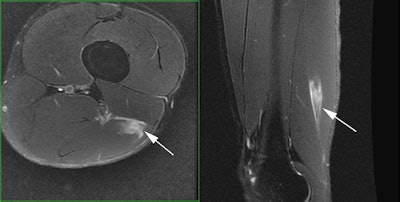

Professional tennis player who experienced acute pain along the back of his left thigh during a match. Axial and sagittal fat-saturated T2-weighted MR images demonstrate an acute injury to the distal fibers of the long head of the biceps femoris near its junction with the short head biceps femoris.Tournaments are very intense, with competitions back to back, resulting in a lot of pressure on athletes. "They're peak performers, always on top and under so much internal and external pressure. Pressure is more acute on the younger players now, much more than 10 or 20 years ago," he noted.